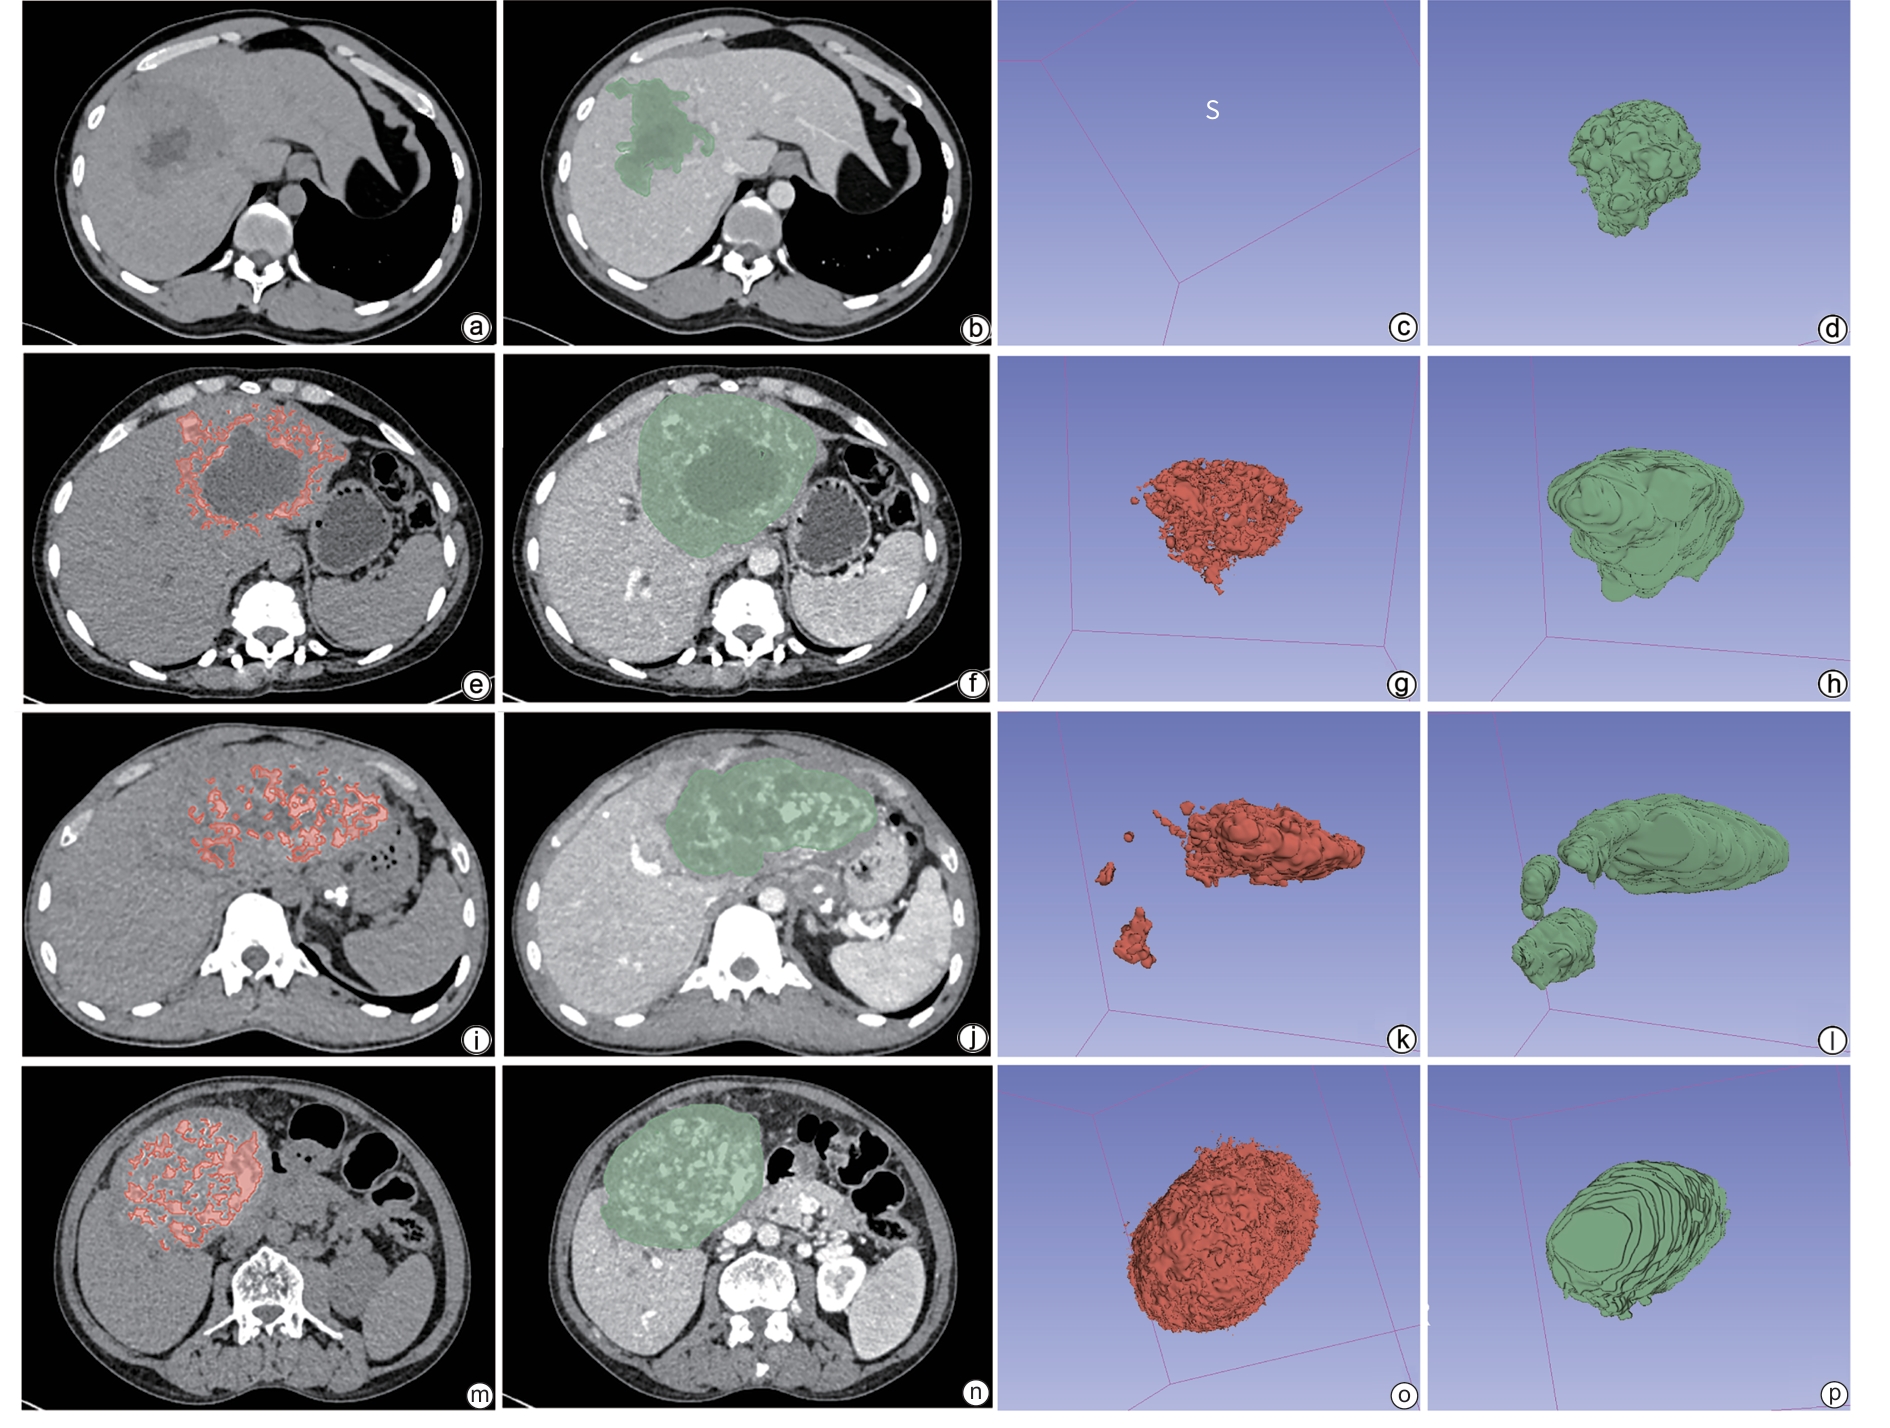

Three-dimensional CT reconstruction of the hepatic pedicle based on the Laennec’s capsule and the development and validation of extra-sheath dissection/occlusion clamp

Zhiyu LIN, Xin XIA, Huan LEI, Yuchuan LUO, Long CHENG, Hongyin LIANG, Tao WANG

2025, 41(10): 2118-2124. DOI: 10.12449/JCH251023

Abstract:

Objective  To investigate the anatomical features of three-dimensional (3D) reconstruction of the hepatic pedicle based on the Laennec’s capsule, as well as its application value in the development of extra-sheath dissection/occlusion clamp and precise hepatectomy.  Methods  A retrospective analysis was performed for the abdominal contrast-enhanced CT data of 100 patients without anatomical abnormalities of the hepatic pedicle in The General Hospital of Western Theater Command from January 2021 to June 2024. The Hisense CAS system combined with the 3D U-net deep learning algorithm was used for 3D reconstruction of the hepatic pedicle at the level of Laennec’s capsule, and the hepatic pedicle was measured in terms of the length, outer diameter, and angle of the main trunk and branches. An extra-sheath hepatic pedicle dissection/occlusion clamp was developed based on the above measurements, and a total of 30 patients scheduled for right hemihepatectomy were enrolled and randomly divided into device group and control group, with 15 patients in each group. The two groups were compared in terms of hepatic pedicle handling time, time of operation, intraoperative blood loss, and the incidence rate of bile duct injury. The independent-samples t test was used for comparison of continuous data between two groups, and the Fisher’s exact test was used for comparison of categorical data between two groups.  Results  The results of 3D reconstruction revealed four variants in the main trunk branches of the hepatic pedicle, with type Ⅰ (left-right branching) accounting for 88% (88/100), type Ⅱ (trifurcation type) accounting for 5% (5/100), type Ⅲ (right anterior branching) accounting for 5% (5/100), and type Ⅳ (special type) accounting for 2% (2/100). The outer diameter of the main hepatic pedicle was 24.10±6.16 mm, the length of the left main branch was 20.59±6.38 mm, and the length of the right main branch was 21.99±7.98 mm. Compared with the control group, the device group had significantly shorter hepatic pedicle handling time (14.10±1.30 minutes vs 17.50±2.00 minutes, t=-5.620, P=0.001) and time of operation (217.00±28.28 minutes vs 241.87±19.49 minutes, t=-2.804, P=0.009). The device group had a significantly lower incidence rate of bile duct injury than the control group (0 vs 20%, P=0.031).  Conclusion  3D reconstruction based on the Laennec’s capsule can accurately display the anatomical variations of the hepatic pedicle. The extra-sheath hepatic pedicle dissection/occlusion clamp developed based on such data can optimize the process of hepatic pedicle management and improve surgical safety, and therefore, it holds promise for clinical application.